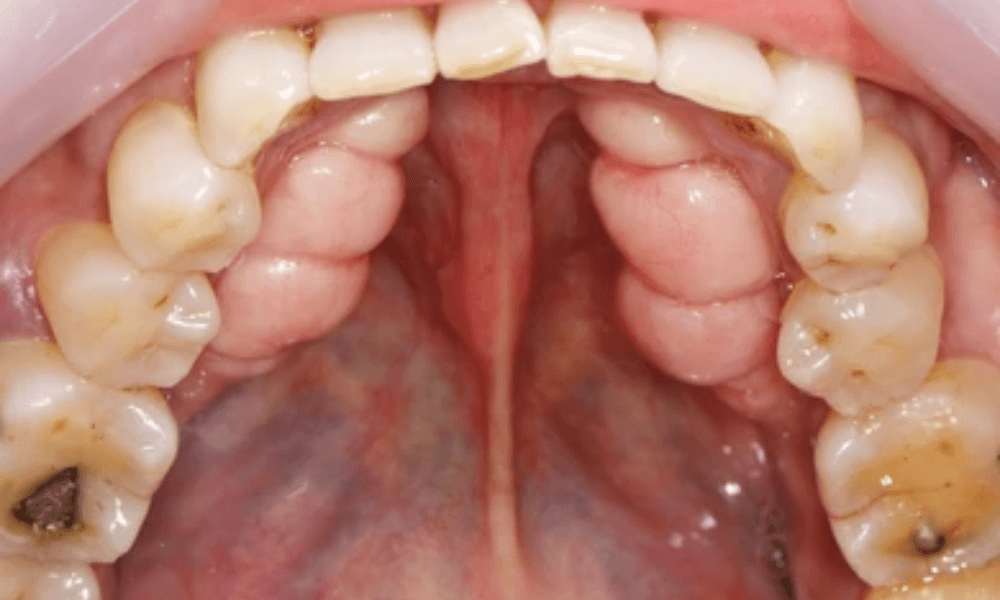

Mandibular Tori Pictures

Mandibular tori are bony growths that appear on the inner surface of the lower jaw. These growths are typically harmless and vary in size and shape. In the pictures provided below, you can observe the different presentations of mandibular tori. These images will help you recognize what mandibular tori look like and understand their typical appearance. If you notice similar growths in your mouth, it’s advisable to consult a dentist for a professional evaluation.